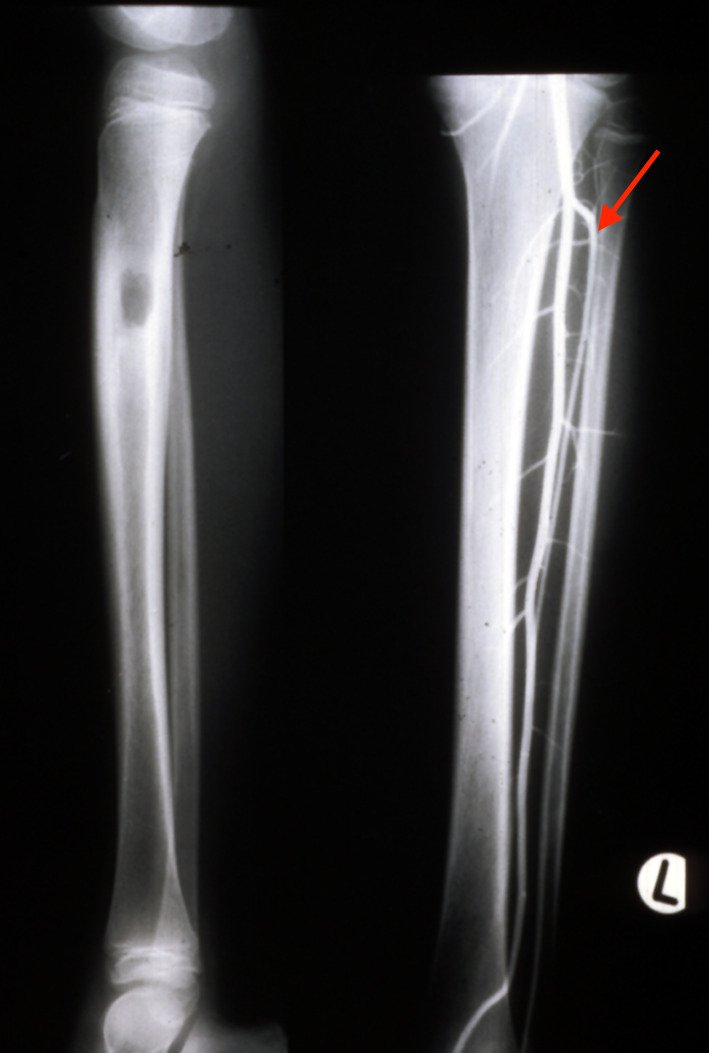

In 1983, a nine-year-old girl presented with a Ewing’s tumour of the right tibial diaphysis (Figure 10 left). She was treated initially with chemotherapy for 12 months with a good result. Segmental resection of the tibia was contemplated and we were invited by Ian Torode and Bob Dickens to consider a fibula reconstruction at the Royal Children’s Hospital Melbourne. Preoperative angiography however, revealed a single peronea magna supplying the foot in the other donor leg. The anterior tibial artery was diminutive (Figure 10 right) but was considered to be of a sufficient size to nourish the fibula transplant.

An 18 cm length of fibula was detached and transferred to bridge the 15 cm defect in the tibia. Periosteum was stripped from the distal end, dowelled into the tibia and secured with a screw. The proximal end was abutted against the underside of the growth plate of the tibia, balanced like a saucer on the end of a pole, and stabilised with an external fixateur (Figure 11A).

At three months the distal end of the fibula graft had united to the tibia. The fixateur was removed leaving behind the transfixing pins that were fixed into an above-knee plaster cast. At eight months the cast was removed, the limb placed in a caliper and weight bearing commenced. Union was noted at the upper end (Figure 11B). By two years dramatic hypertrophy of the transplanted fibula was noted together with growth from the proximal epiphysis (Figure 11C). The limbs had almost identical length (Figure 12), the knee and ankle joints were normal and the only disability was temporary weakness of the EDL in the donor leg.